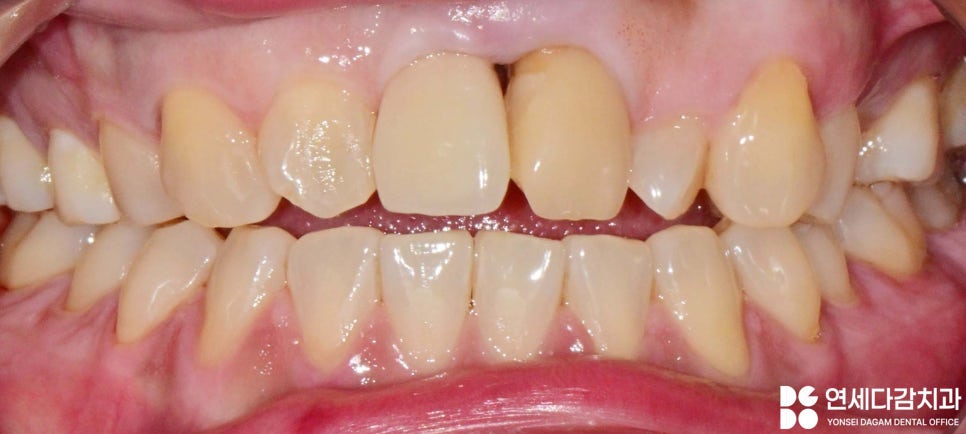

개방교합은 위아래 앞니가 서로 닿지 않아

음식물을 끊는 기능이

어려운 상태를 말합니다.

이러한 개방교합이 심하고

치아 배열이 가지런하지 않다면

심미성에 큰 영향을 주고,

저작 기능에도 영향을 미칠 수 있습니다.

개방교합일 경우 앞니가

닿지 않아 발음이나 식사에

어려움이 있을 수 있습니다.